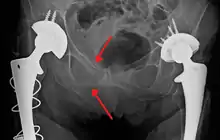

The most common causes of blunt pelvic trauma are motor vehicle crashes and multiple-story falls, and thus pelvic injuries are commonly associated with additional traumatic injuries in other locations.[27] In the pelvis specifically, the structures at risk include the pelvic bones, the proximal femur, major blood vessels such as the iliac arteries, the urinary tract, reproductive organs, and the rectum.[28][27]

.png.webp)

One of the primary concerns is the risk of pelvic fracture, which itself is associated with a myriad of complications including bleeding, damage to the urethra and bladder, and nerve damage.[29] If pelvic trauma is suspected, emergency medical services personnel may place a pelvic binder on patients to stabilize the patient's pelvis and prevent further damage to these structures while patients are transported to a hospital. During the evaluation of trauma patients in an emergency department, the stability of the pelvis is typically assessed by the healthcare provider to determine whether fracture may have occurred. Providers may then decide to order imaging such as an X-ray or CT scan to detect fractures; however, if there is concern for life-threatening bleeding, patients should receive an X-ray of the pelvis.[30] Following initial treatment of the patient, fractures may need to be treated surgically if significant, while some minor fractures may heal without requiring surgery.[27]

A life-threatening concern is hemorrhage, which may result from damage to the aorta, iliac arteries or veins in the pelvis. The majority of bleeding due to pelvic trauma is due to injury to the veins.[29] Fluid (often blood) may be detected in the pelvis via ultrasound during the FAST scan that is often performed following traumatic injuries. Should a patient appear hemodynamically unstable in the absence of obvious blood on the FAST scan, there may be concern for bleeding into the retroperitoneal space, known as retroperitoneal hematoma. Stopping the bleeding may require endovascular intervention or surgery, depending on the location and severity.[28]